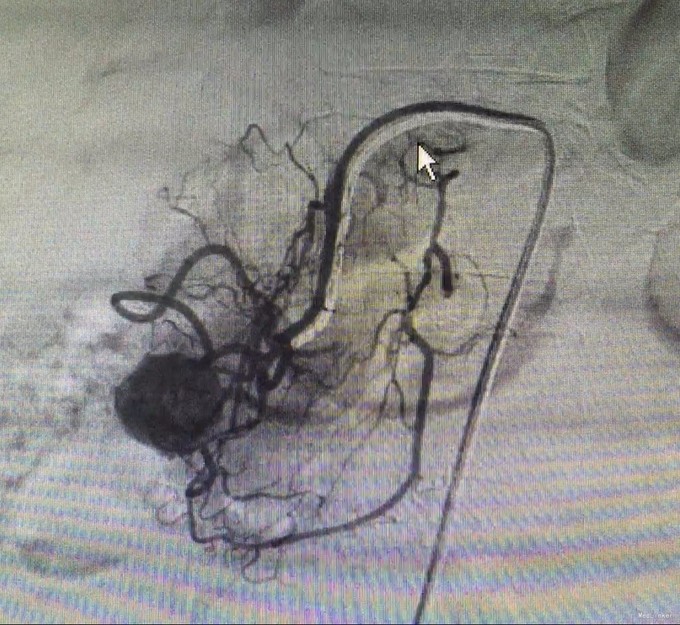

查体:神清,腹软,未及包块,无压痛及反跳痛,神经系统检查未见异常 辅查:外院头颅CT平扫:腔隙性脑梗;胰腺CT平扫:胰头、十二指肠降部稍低密度影,肝内多发小囊肿;上腹部增强CT:胰腺低密度影,考虑良性;肝内多发小囊肿。 入院检查:血、尿、粪常规、肝肾功能、电解质、凝血功能正常;AFP、CEA、CA19-9、CA125、CA15-3、CA72-4均正常;胰岛素78.33mIU/L,C肽 4.91ug/L。腹腔动脉DSA:胰头区富血供肿瘤; 胰腺增强MRI:1、胰头部富血供病变,考虑胰岛素瘤可能性大;2、肝内多发小囊肿。